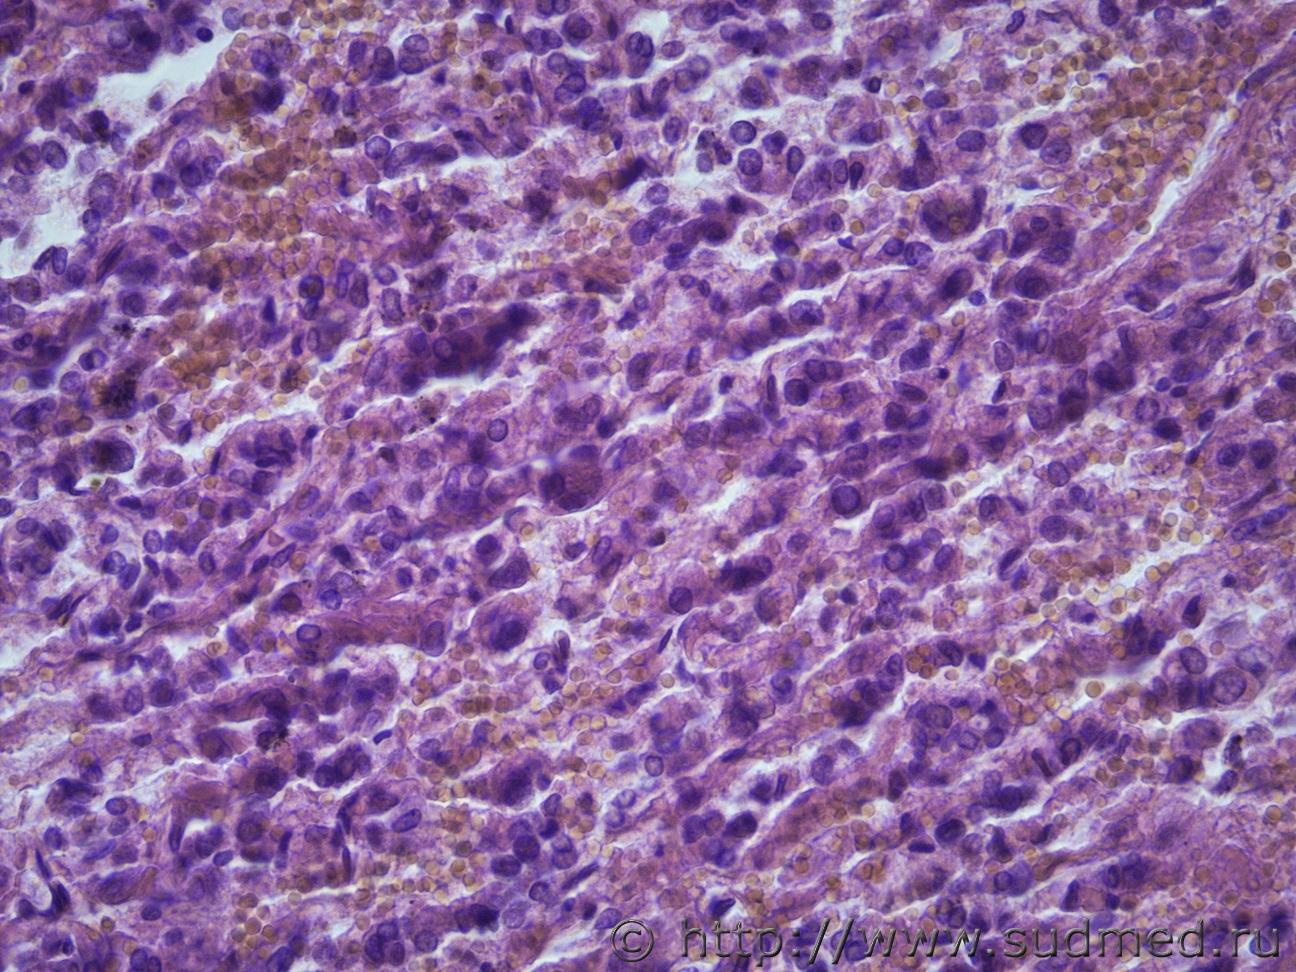

Ув. коллеги, нужна ваша помощь. Опухолевидное образование правой доли Щ.Ж. Жен. 60 лет Судебная медицина - Прикрепленное изображение Судебная медицина - Прикрепленное изображениеСудебная медицина - Прикрепленное изображениеСудебная медицина - Прикрепленное изображениеСудебная медицина - Прикрепленное изображение

Сложный орган. По-моему, идет образование фолликулов.

Похоже на недифференцированный рак.

Парное совпадение и щитовидке и в почке с мтs в легкие и в предыдушем вашем случае медуллярная карцинома